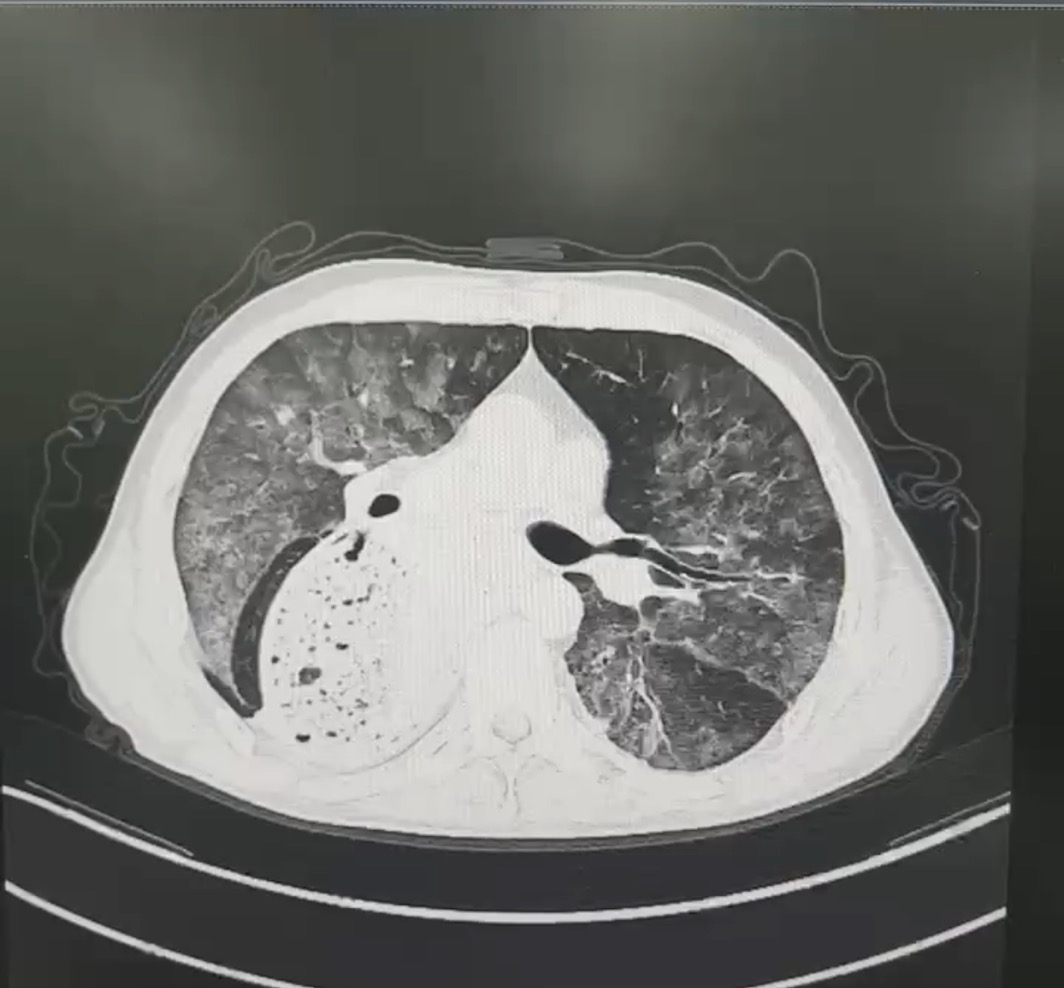

患者赵先生,反复的胸闷、呼吸困难一年有余,每一次呼吸都成为一种负担。随着时间推移,病情逐渐恶化,平静休息时难以缓解,活动后症状加剧。赵先生曾辗转多家医院就诊,然而疾病始终诊断不明,治疗效果不佳,病情时有反复,令患者和家属备受煎熬。近期,患者的病情急转直下,胸闷气急加重,甚至出现呼吸衰竭。门诊胸部CT提示两肺弥漫性渗出病变,紧急收入我院。

胸部CT

入院后,医生迅速展开全面细致的检查,支气管镜检查发现患者肺泡灌洗液成米汤样,并具有明显分层现象,结合后续肺泡灌洗液报告,中性粒细胞占比高达99.0%,并可见吞噬细胞,镜下可见大量脂肪空泡,苏丹 III 染色呈阳性,这些证据指向疾病的最终真相——脂质性肺炎。